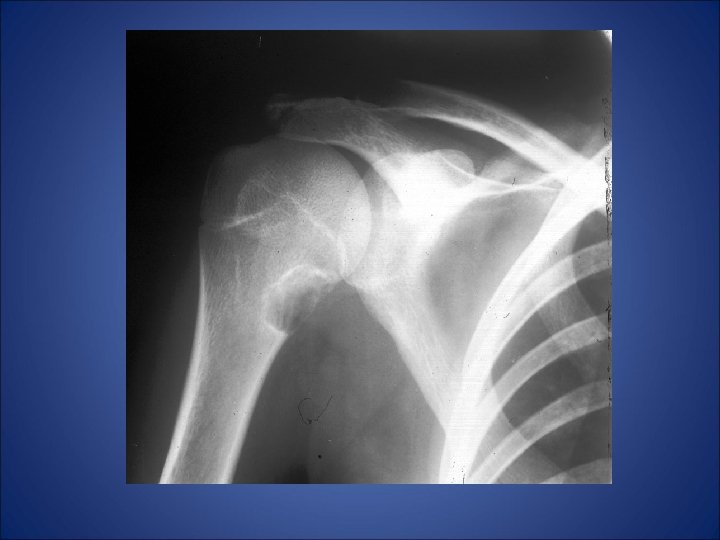

• A 26 yrs old male presented with complaint of pain in left shoulder after lifting a heavy weight. • His x-ray of left shoulder was taken which revealed…

Shows slightly expansile, septated lytic lesion is present involving the proximal 1 /3 rd of the left humerus. The margins are not sclerotic. The epiphysis appears uninvolved.

The most likely differentials would be: • Unicameral bone cyst • Aneurysmal bone cyst • Enchondroma • Fibrous dysplasia • Myxoid fibroma.

Radiolucent lesion with expanded cortex arising in medullary canal of metaphysis of humerus -aneurysmal expanded appearance of cortex is contained by periosteum & thin shell of bone; -Marked cortical thinning and erosion and periosteal elevation